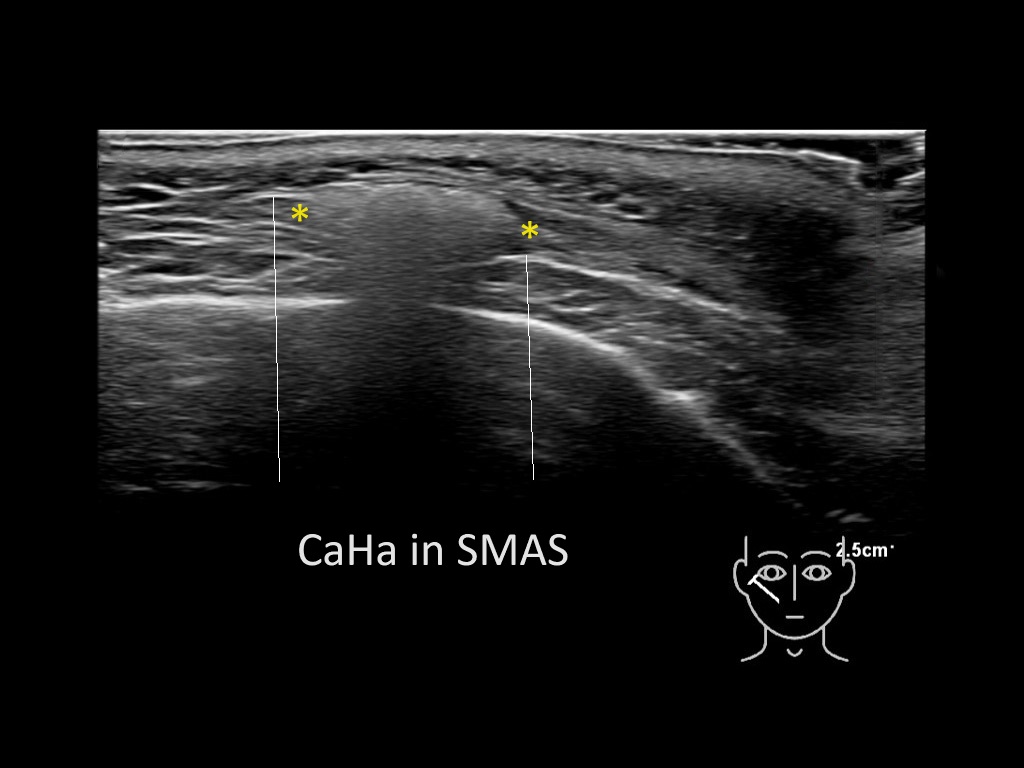

Filler deposits may end up unintentionally in the SMAS or fascial layers of the skin. Very often this will not lead to adverse events, however, adverse events ( nodules, migration / redistribution impaired muscle movement and smiling and malar edema) are are often related to filler ending up in the SMAS or fascia.

Study the first image to recognize the different layers. If you are sure about the layers, swipe to the second image to view the answer (if applicable).